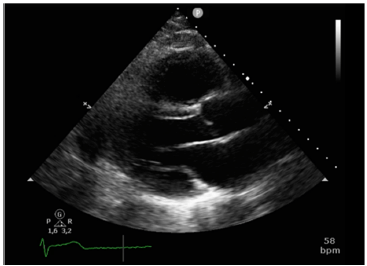

Analise a figura a seguir.

As cúspides aórticas vistas nessa imagem são: